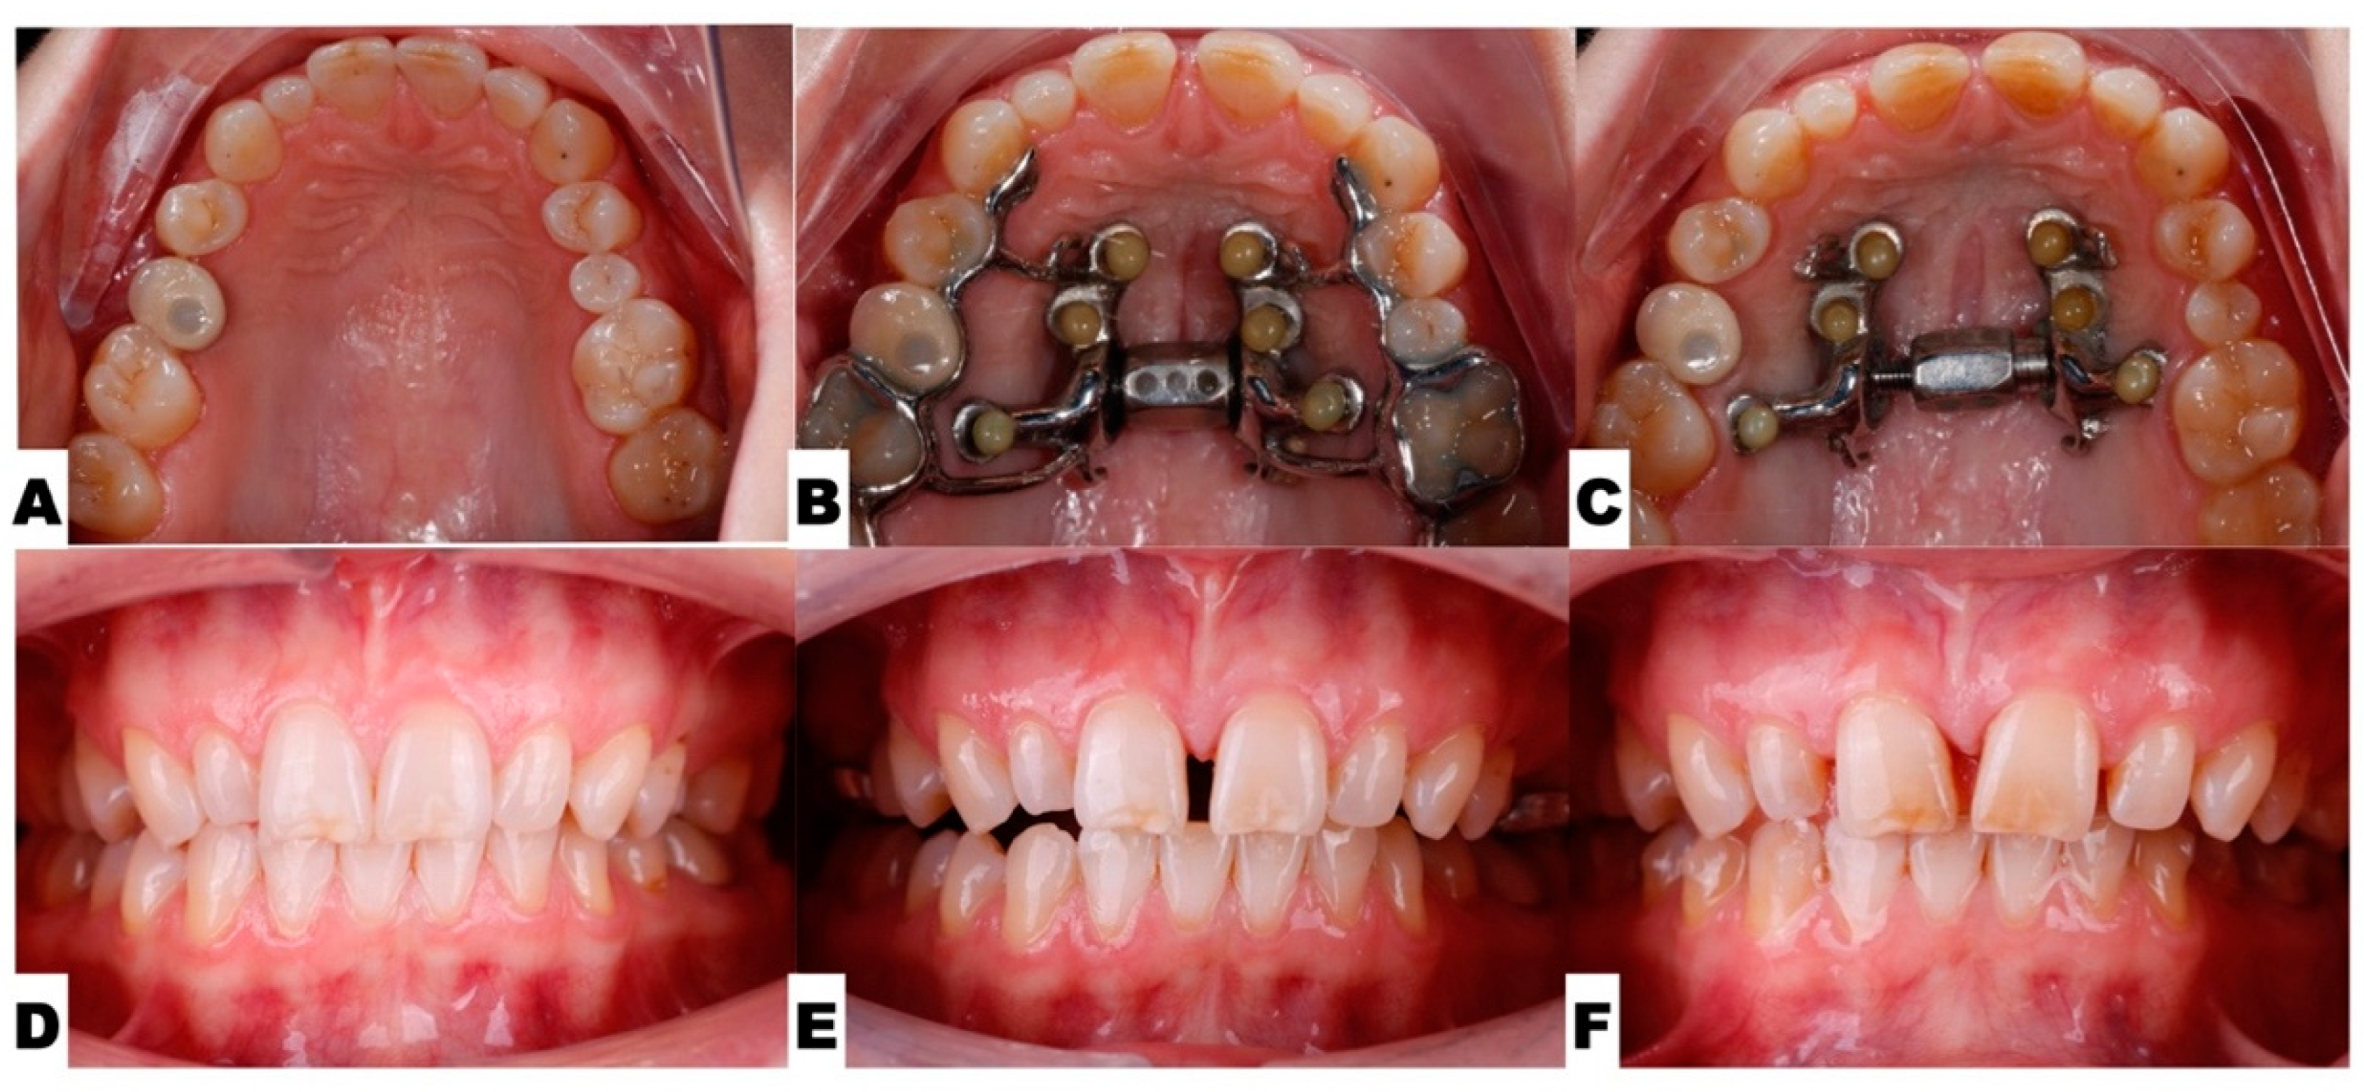

2.3. Procedures and Appliances

2.3.1. Surgical Protocol

2.3.4. Postoperative Assessment, Outcome Analysis, and Asymmetry Correction

2.4. Pre-Restorative Records